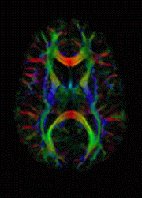

He also gives diffusion tensor imaging a go:

A second MR technique, diffusion tensor imaging, provides another valuable measurement of the brain. While fMRI provides information about brain signals, DTI provides insight about the properties of brain structures. DTI has been particularly important in determining which parts of the brain are connected to one another

Diffusion tensor imaging

And, these combinations of structure- and function measurements on awake human brains are, of course, a relatively new thing that has allowed us to clarify our theories about how the brain actually works...